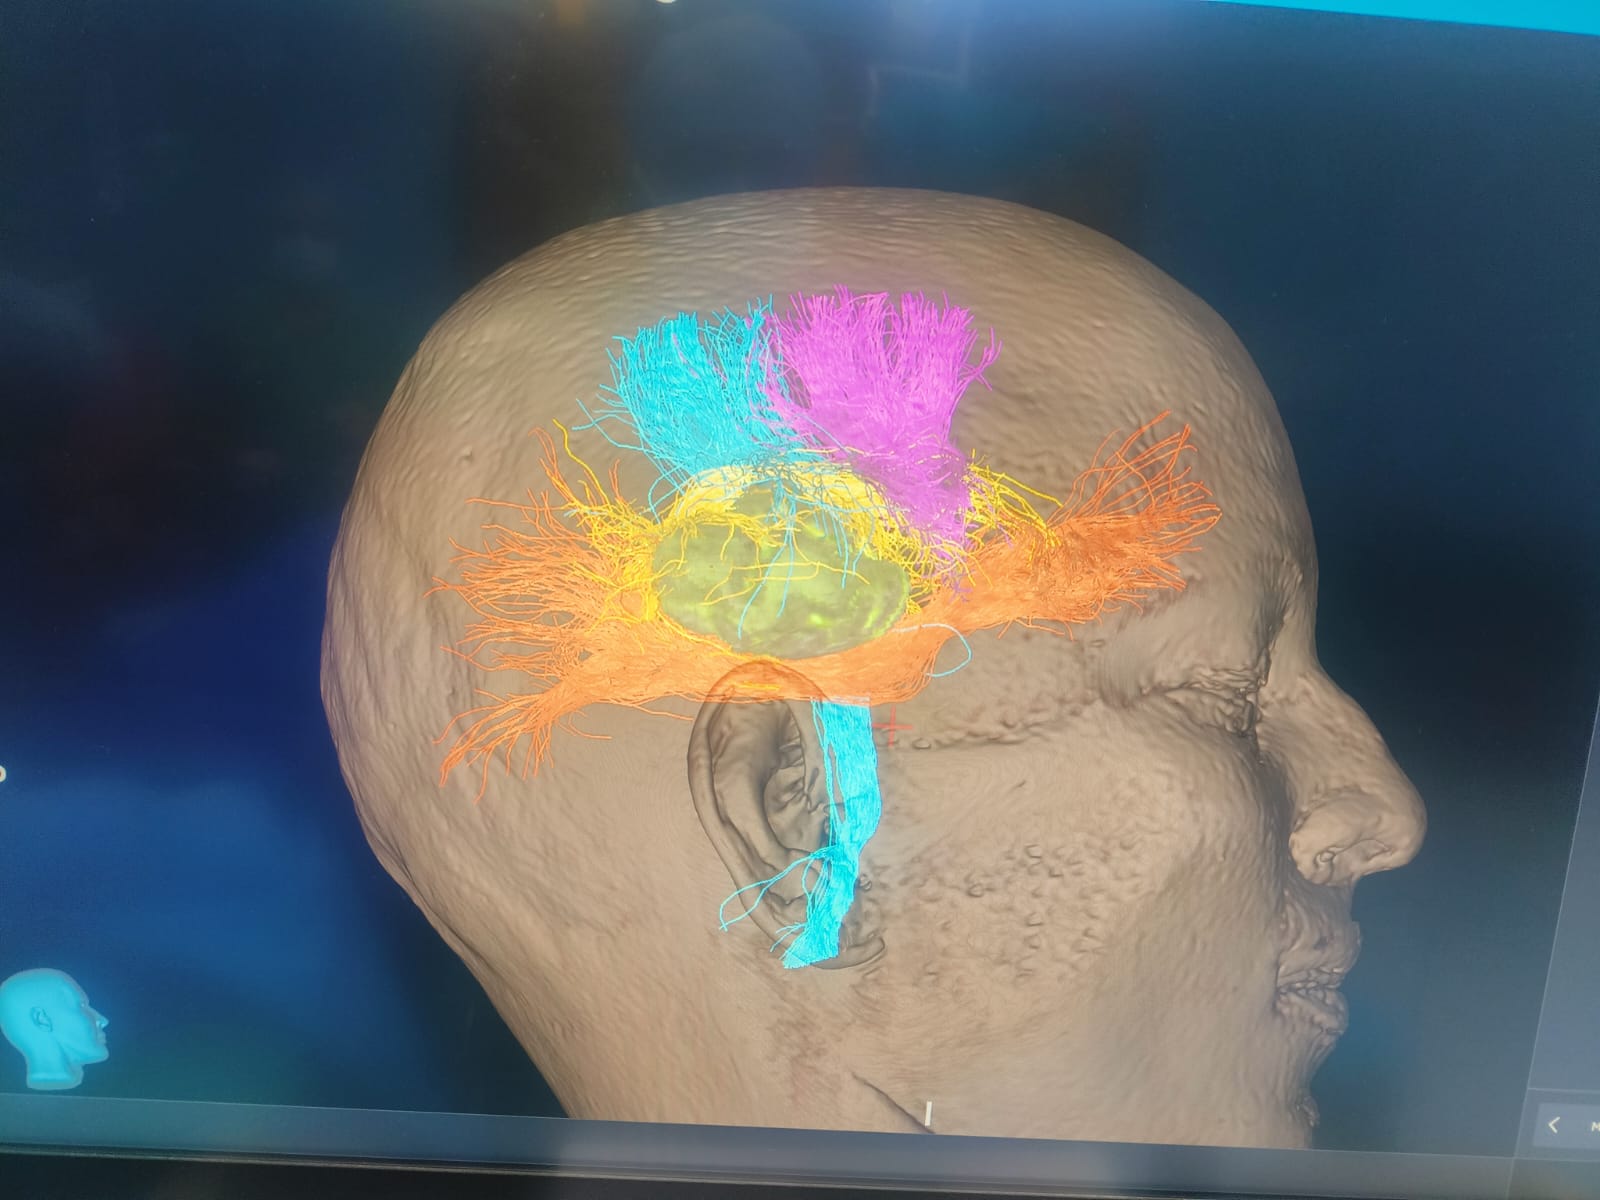

Brain and Spinal Avm

Brain Tumor Surgery